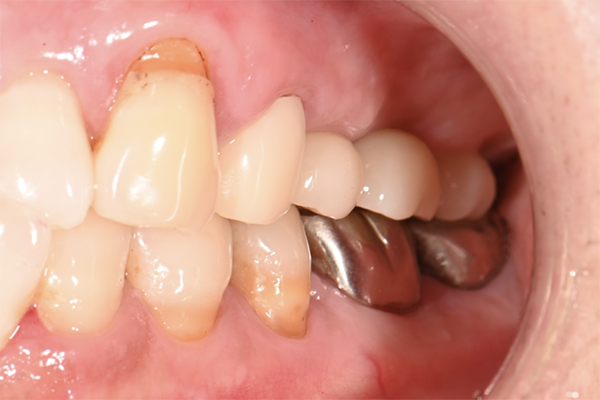

| 主訴 | 奥歯で噛めない、顎が痛い |

|---|---|

| 治療内容 | 奥歯のインプラント治療、前歯・奥歯の被せ物治療 |

| 治療期間 | 6ヶ月 |

| 治療費 | 350万円 |

| 治療リスク | 被せ物をつけた初期の段階で歯がしみることがある(時間とともに改善する) インプラント治療後に3日程度痛みと腫れを伴うことがある |